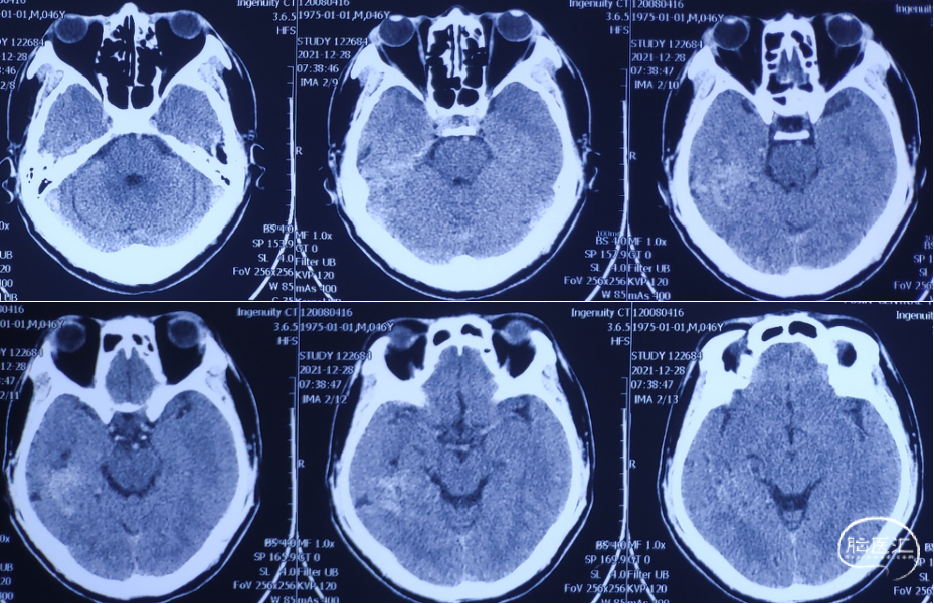

术前CT